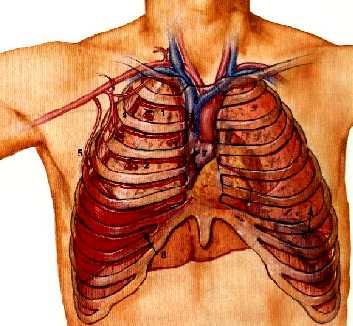

Un paciente varón de 73 años ingresa en Urgencias inconsciente, después de un accidente de tráfico, con fracturas de 3ª,4ª,5ª y 6ª costillas derechas y fractura diafisaria de femur izquierdo.

El paciente presenta dísnea intensa y cianosis.

Radiografia de tórax: hemotórax derecho y contusión pulmonar